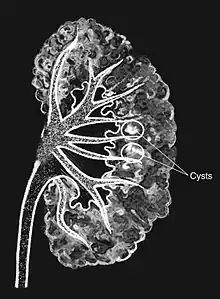

| Medullary sponge as seen on an intravenous pyelogram | |

Classically, MSK is seen as hyperechoic papillae with clusters of small stones on ultrasound examination of the kidney or with an abdominal x-ray. The irregular (ectatic) collecting ducts are often seen in MSK, which are sometimes described as having a "paintbrush-like" appearance, are best seen on intravenous urography. However, IV urography has been largely replaced by contrast-enhanced, high-resolution helical CT with digital reconstruction.[8]